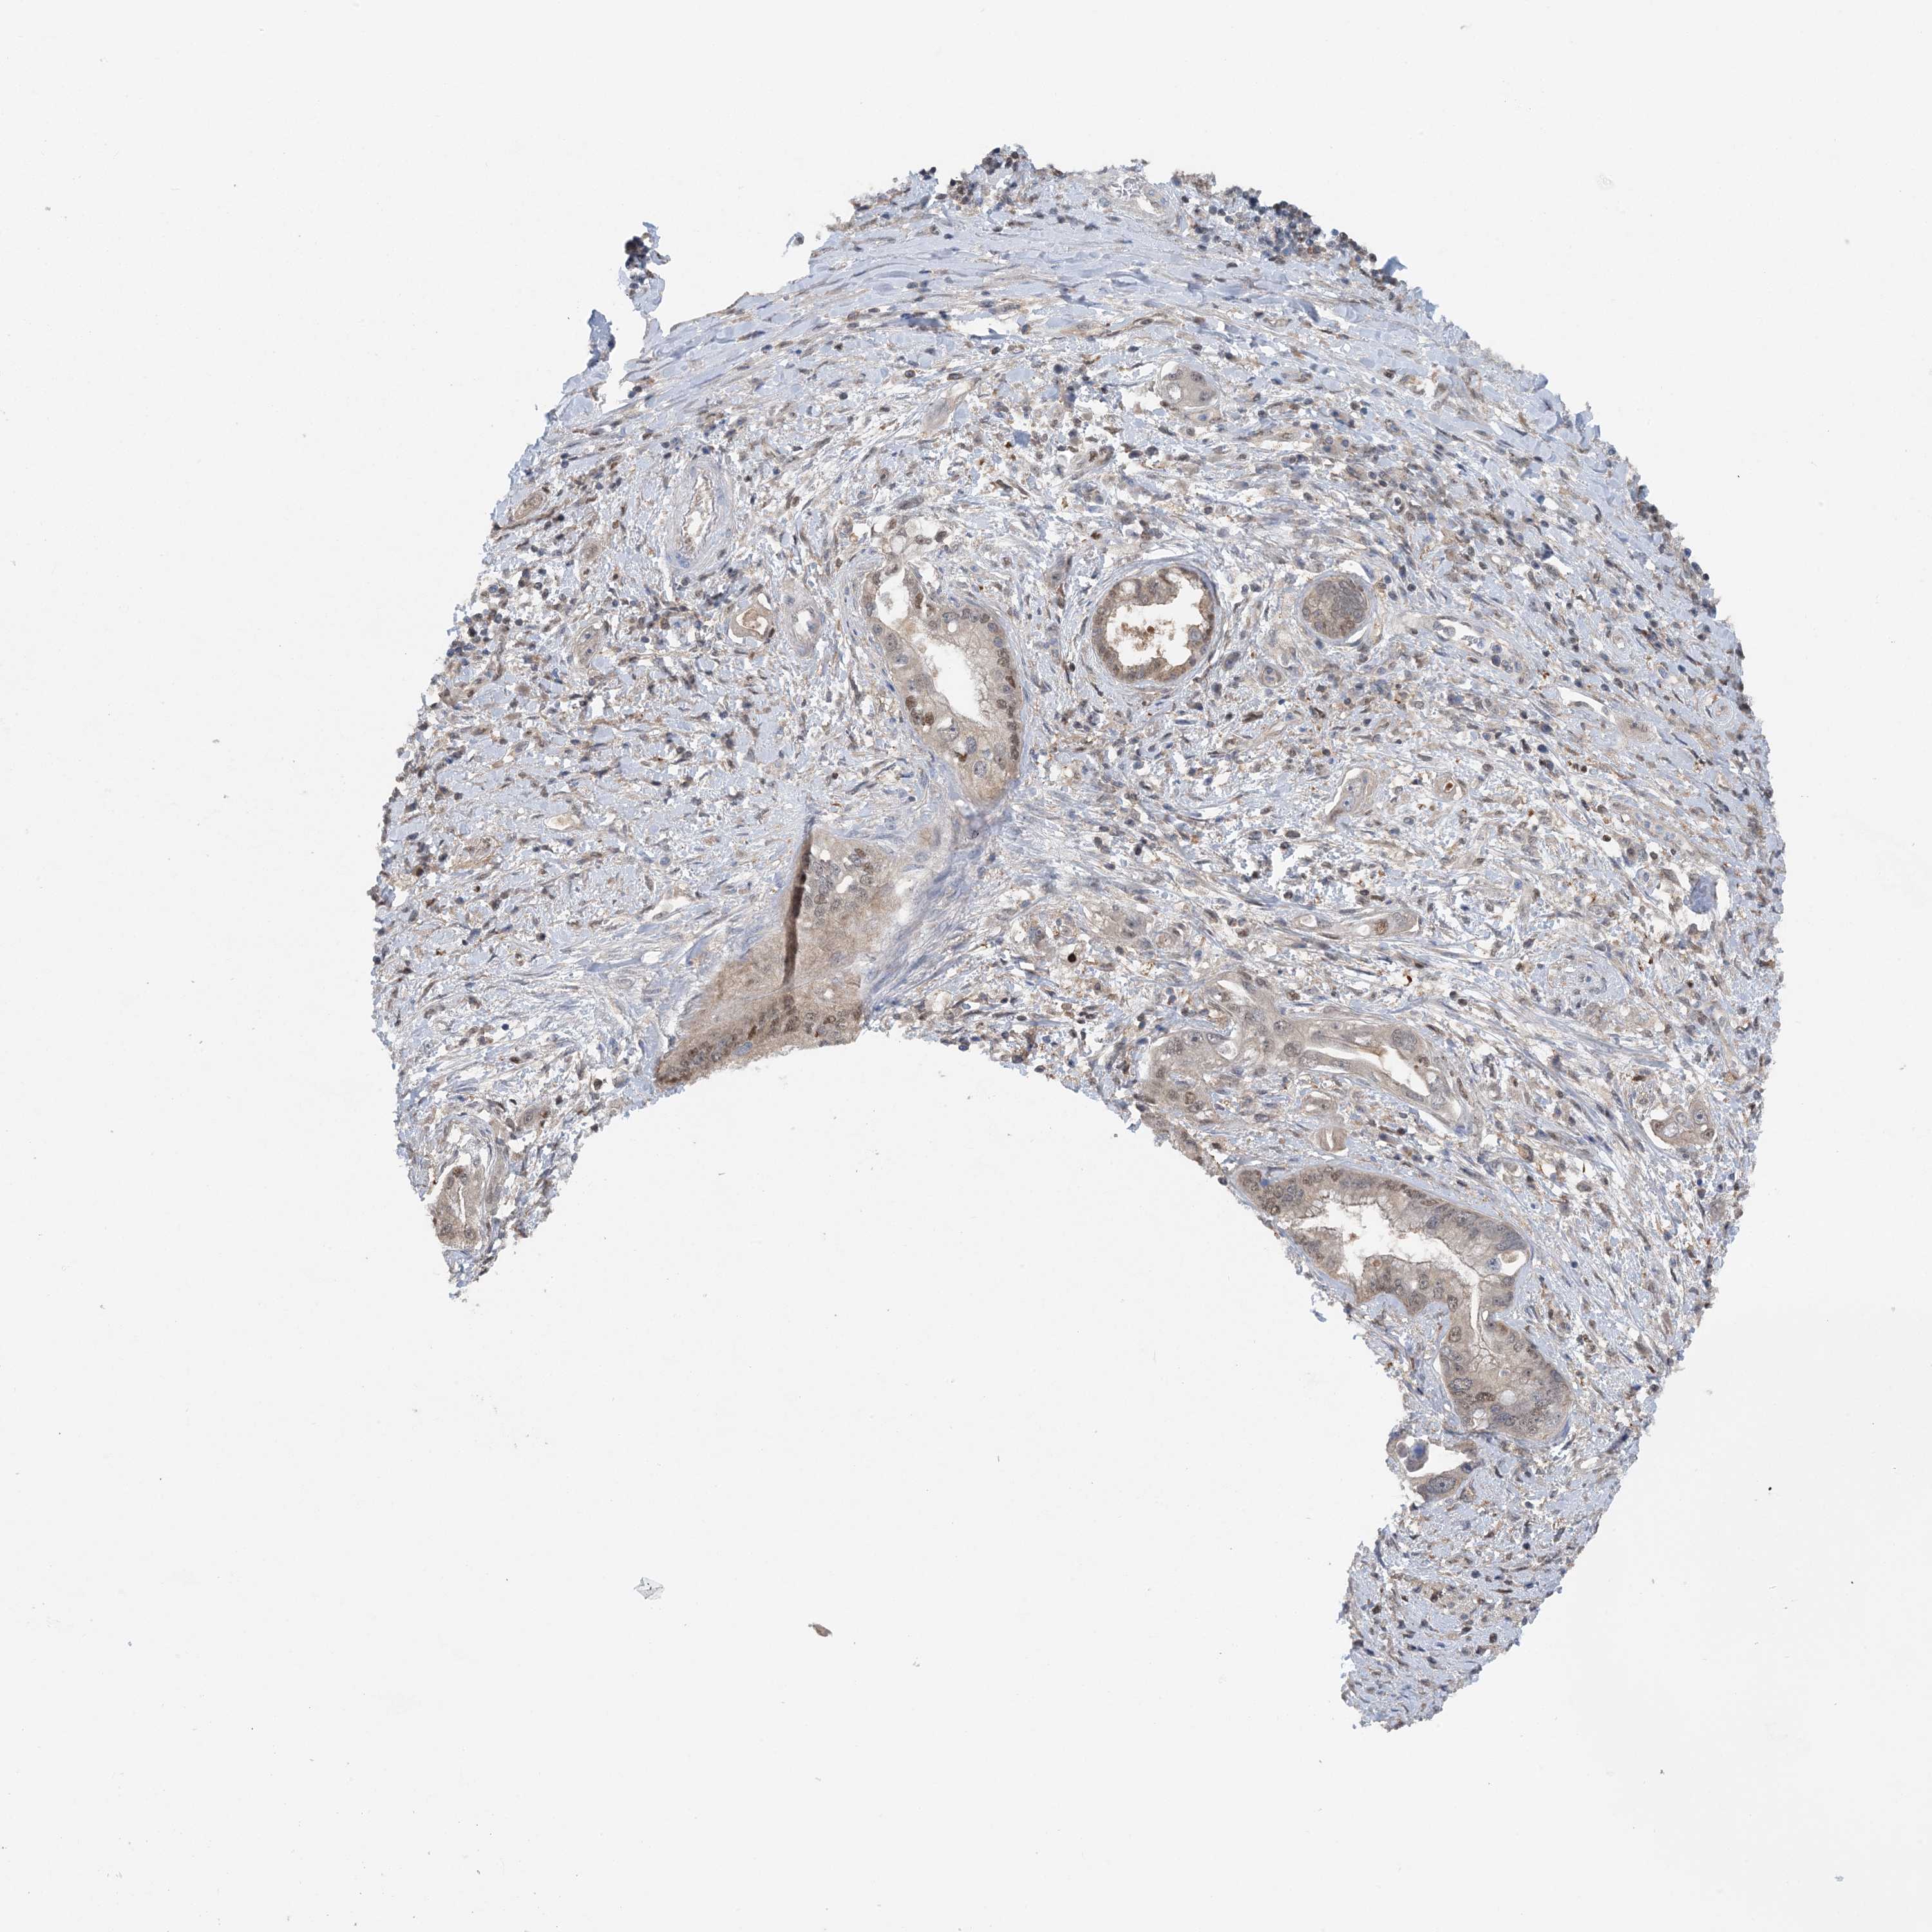

PANCREATIC CANCER - Protein expressioni

A mouse-over function shows sample information and annotation data. Click on an image to view it in a full screen mode. Samples can be filtered based on level of antibody staining by selecting one or several of the following categories: high, medium, low and not detected. The assay and annotation is described here.

Note that samples used for immunohistochemistry by the Human Protein Atlas do not correspond to samples in the TCGA dataset.

Antibody stainingi

Antibody staining in the annotated cell types in the current human tissue is reported as not detected, low, medium, or high, based on conventional immunohistochemistry profiling in selected tissues. This score is based on the combination of the staining intensity and fraction of stained cells.

Each image is clickable and will lead to virtual microscopy that enables deeper exploration of all samples and also displays staining intensity scores, fraction scores and subcellular localization as well as patient and tissue information for each sample.

Antibody HPA035063

Antibody HPA035064

Staining

High

Medium

Low

Not detected

Intensity

Strong

Moderate

Weak

Negative

Quantity

>75%

75%-25%

<25%

None

Location

Nuclear

Cytoplasmic/membranous

Cytoplasmic/membranous,nuclear

Adenocarcinoma, NOS